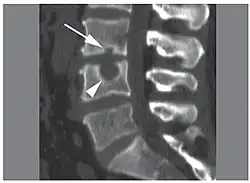

Schmorl's nodes can be detected with X-rays, although they can be imaged better by CT or MRI. They are considered to be vertical disc herniations through the cartilaginous vertebral body endplates. Schmorl's nodes can sometimes be seen radiographically, however they are more often seen on MRI, even when not visible on plain X-rays. They may or may not be symptomatic, and their etiological significance for back pain is controversial. In a study in Spine by Hamanishi, et al., Schmorl's nodes were observed on MRI in 19% of 400 patients with back pain, and in only 9% of an asymptomatic control group. The authors concluded that Schmorl's nodes are areas of "vertical disc herniation" through areas of weakness in the endplate.[4]